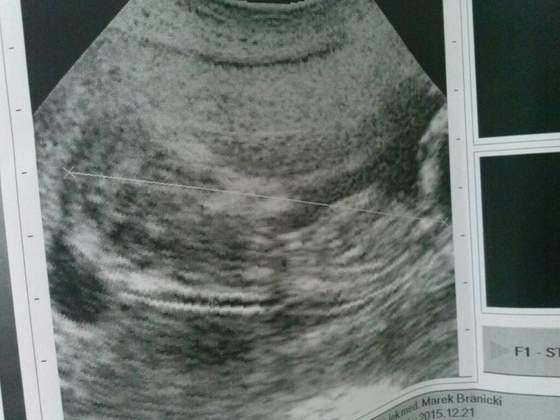

To moje małe ufo :)

Inna bajka faktycznie jakość kiepska, najważniejsze że można odczytać co i jak, kiedyś nawet tego nie było. Mój w pierwszej ciąży tez miał kiepski sprzęt ale jednak trochę lepszy ;)